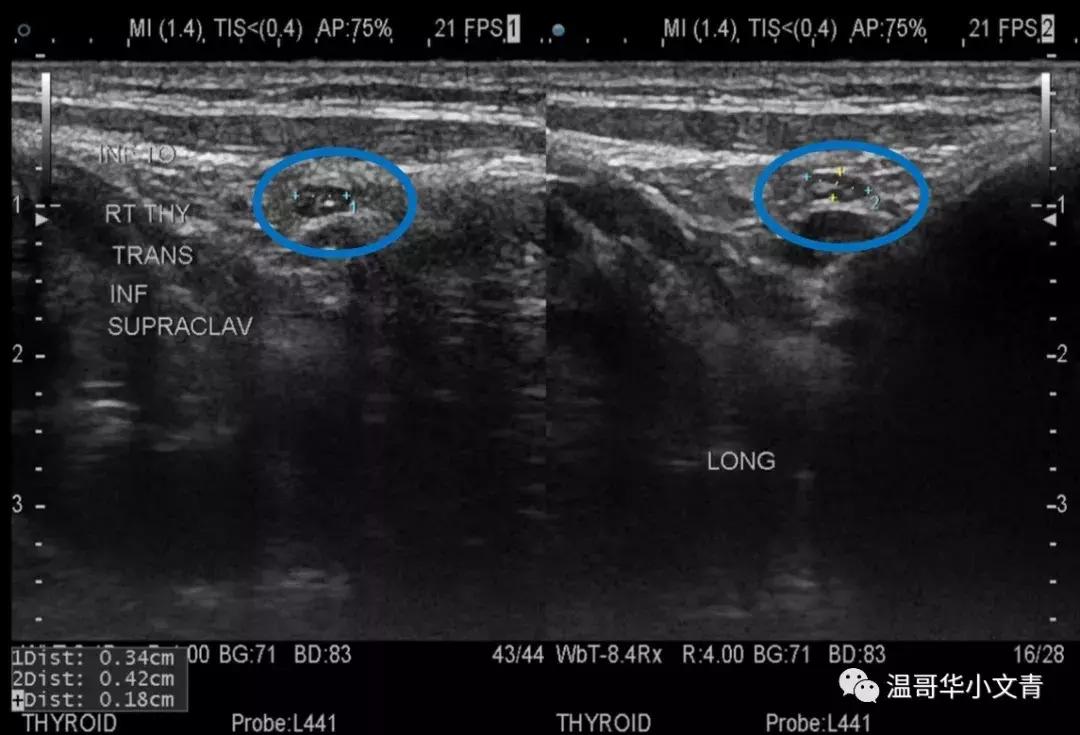

第二个图是一个术前发现的气管前可疑淋巴结,淋巴结长径是8毫米。这个淋巴结也是比较圆,而且内部还能看到一些小的囊性化的成分,基本证明了这是一个转移淋巴结,术后病理显示这个淋巴结里的转移灶是8毫米。

第三个图是一个术前发现的气管旁甲状腺下方可疑淋巴结,淋巴结长径是4毫米。在这个淋巴结中间你能看到明显的钙化,基本证明了这是一个转移淋巴结,术后病理显示这个淋巴结里的转移灶是2毫米。